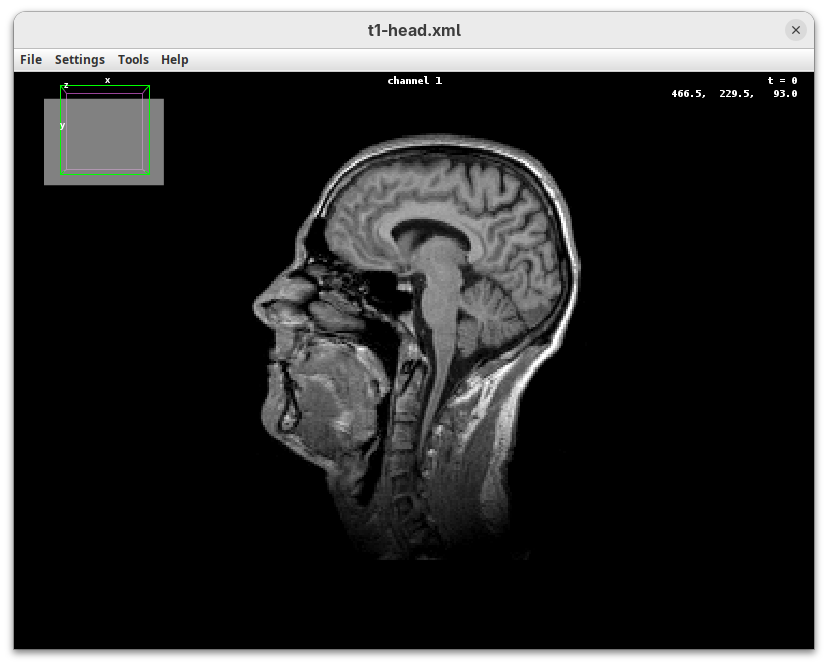

BigDataViewer (Pietzsch et al. 2015) is one of the most important tools for visualizing large, multidimensional datasets. It provides a simple and intuitive interface and shortcuts to swiftly navigate through your sample even on a regular laptop. This is possible because of the underlying file format used by BigDataViewer: the XML/HDF5 combo. Therefore, before opening the plugin, we must convert our dataset.

- Go to

Plugins>BigDataViewer>Export Current Image as XML/HDF5.

A dialog with export options will open.

- Under

Export path, click onBrowseto select the output directory fort1-head.xml.

The export process will start. Since this is a small dataset, it’ll be fast. But, for large datasets, this can take hours.

When done, you will find two new files in your working directory: t1-head.xml and t1-head.h5.

The XML file stores metadata information about the image. The HDF5 file stores actual image data. These two files will always be in a pair. To open the XML/HDF5:

Plugins>BigDataViewer>Open XML/HDF5and select thet1-head.xml.

The BigDataViewer interface will open showing an optical section of the head sample.

Getting familiar with BigDataViewer is an essential skill for navigating large 3D datasets. It’ll also be important for the multiview registration pipeline. So, take the time to learn the basic commands and shortcuts. It is nicely intuitive. The BigDataViewer’s page on the ImageJ Docs has the official documentation and we can also go to Help > Show Help for an up-to-date overview.

Some of the movements to try:

Left-click and drag: turn the sample around the mouse pointer at any arbitrary angle.Right-click and drag: move the sample in the XY plane (of the view).Scroll: move through the Z plane (of the view). UseShift+Scrollto move fast.Ctrl+Shift+Scroll: zoom in or out.

But, most importantly, are the commands to put your sample back to its original orientation or along any of the original dimension axes:

Shift+Z: orient the sample on the XY plane.Shift+X: orient the sample on the ZY plane.Shift+Y: orient the sample on the ZX plane.

Finally, a visual tip. The default interpolation between image slices is nearest-neighbors. Press I to activate the tri-linear interpolation to obtain a much smoother (and improved) data visualization.